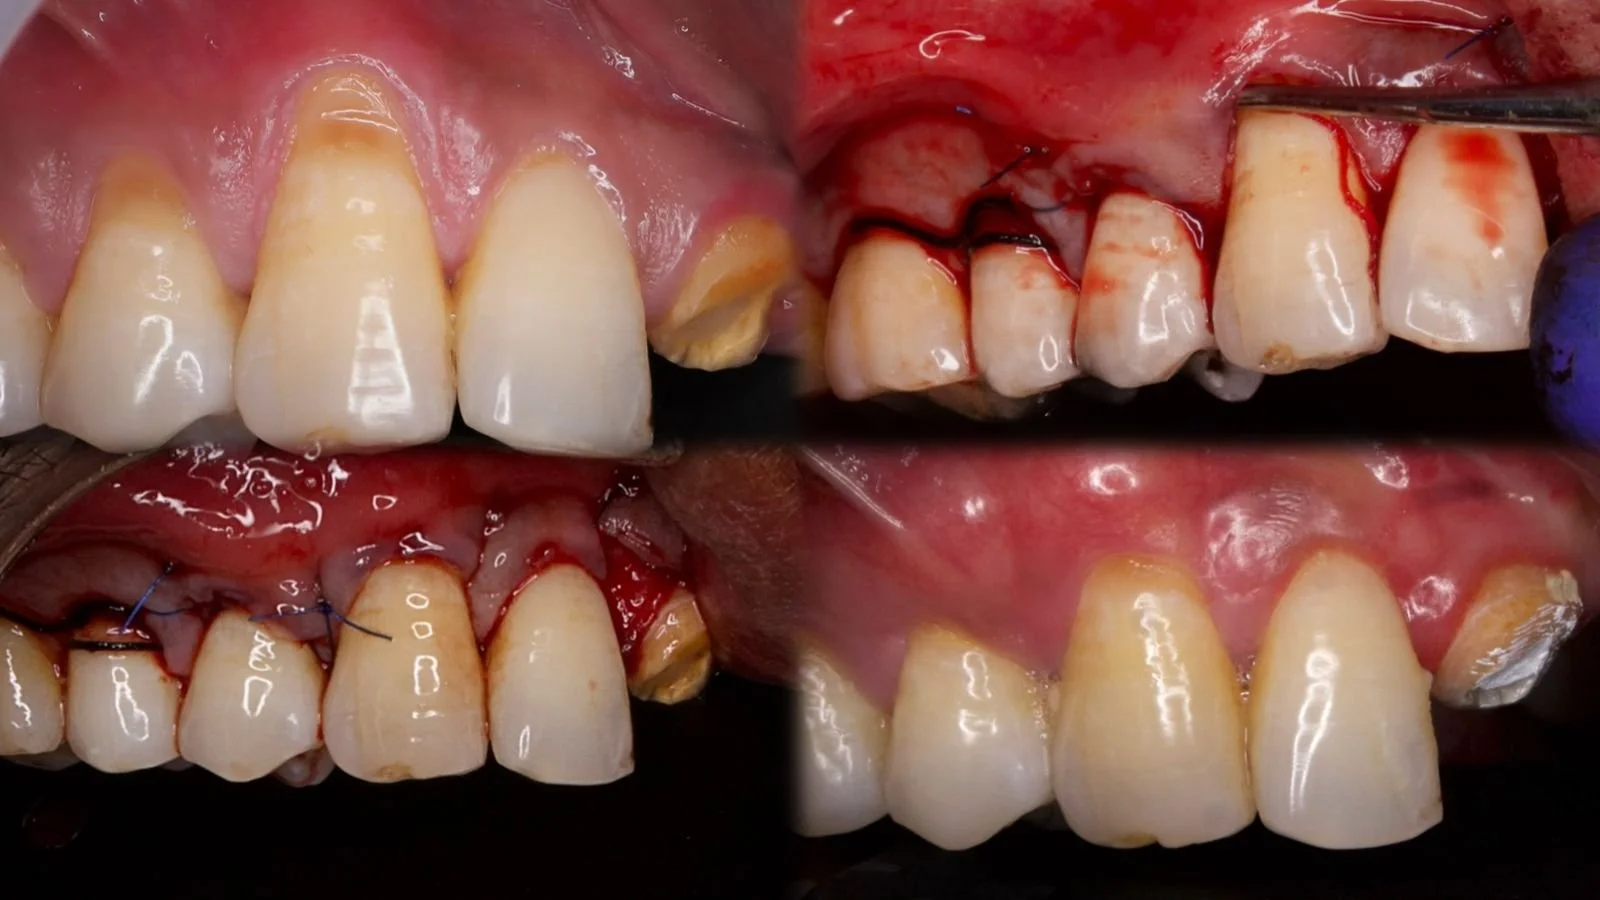

Root coverage with Tunelling and coronally advanced flap

Case done by Dr NIvedha, III year PG

Periodontics SaveethaJanuary 7, 2025